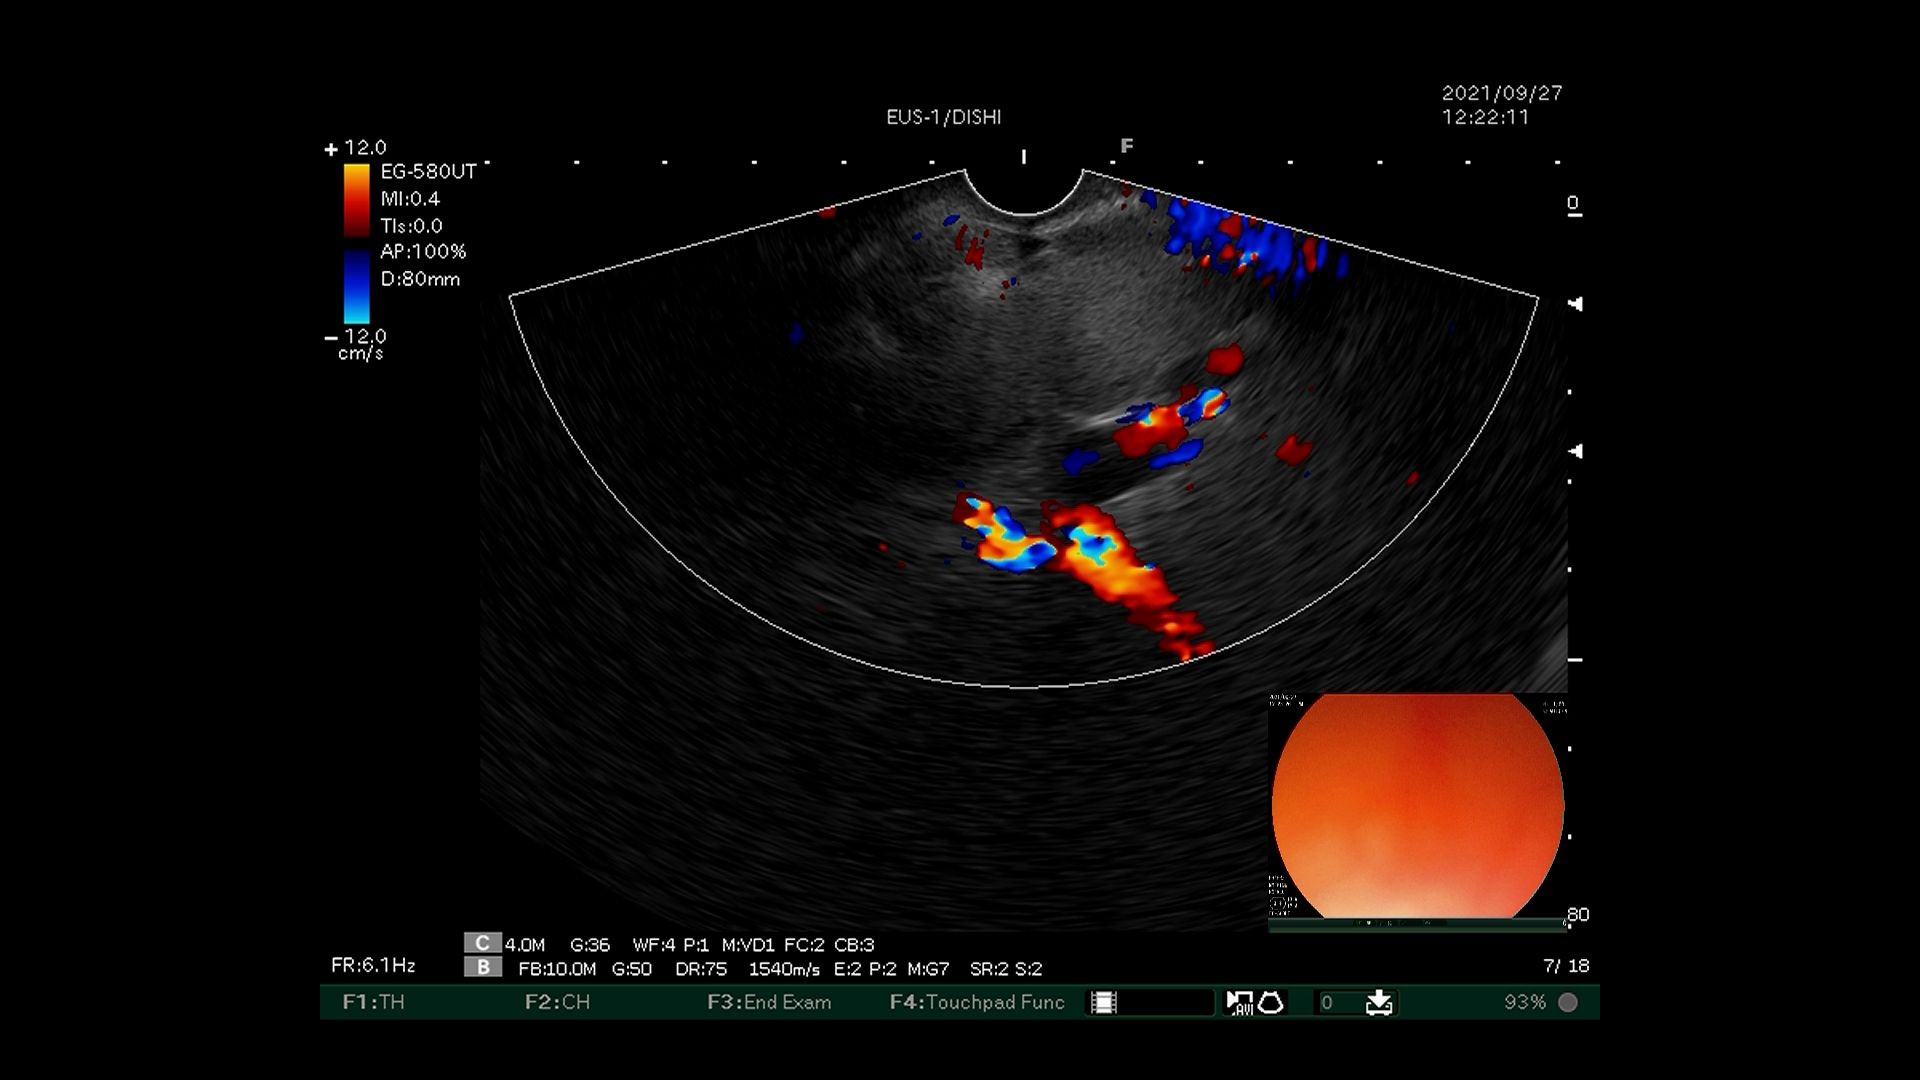

3)超声内镜下多普勒观察内部有丰富血流信号。

6)超声内镜确认曲张静脉血流信号消失。

超声内镜引导下弹簧圈置入联合组织胶栓塞术先使用超声内镜识别胃底曲张静脉,选取曲张静脉内径最宽处,在超声内镜引导下经食管下段、膈肌角以19G穿刺针穿入曲张静脉,置入数枚略大于曲张静脉内径的弹簧圈,然后用“高糖-组织胶-高糖”三明治法于曲张静脉内注射组织胶,最后使用超声内镜确认曲张静脉血流信号消失。该技术可明显降低异位栓塞的风险,但需要手术者同时具有超声内镜及静脉曲张两个亚专业的熟练操作技巧,手术大出血风险极高,若有不慎即可导致术中患者死亡。